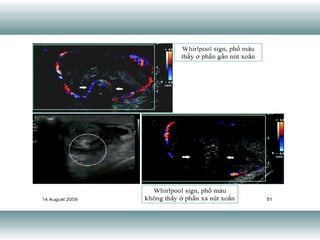

The document is an imaging department report discussing cardiac function measurements. It contains an abbreviation for the ratio of stroke volume (the amount of blood pumped out of the heart with each beat) to end diastolic volume, which is a measurement of cardiac output.